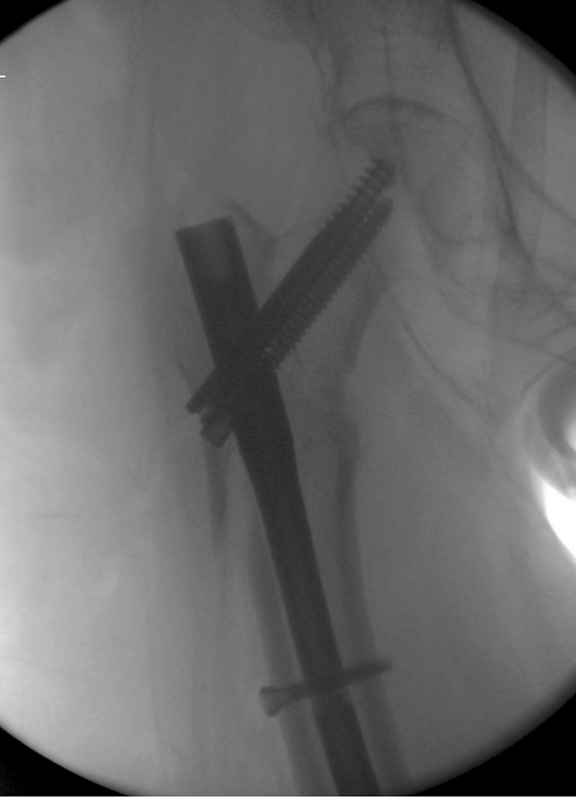

Здесь пара случаев фиксации похожих переломов:

первый высокоэнергетическая травма 36 лет

Djoldas Kuldjanov, M.D.